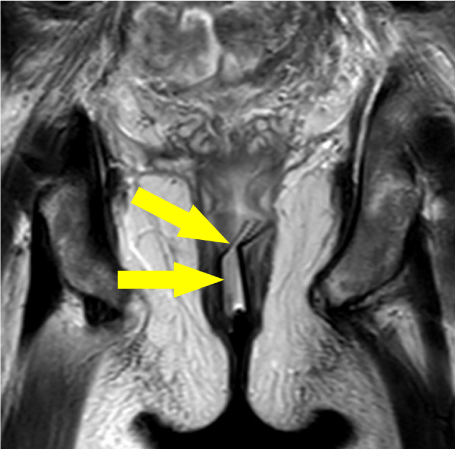

A 50-year-old gentleman whilst undergoing neoadjuvant chemotherapy for rectal cancer underwent an emergency Hartman's procedure for a stercoral perforated rectosigmoid colon. One week post-operatively the patient became persistently pyrexial with rising inflammatory markers, two days after the withdrawal of an abdominal 20 F drain. A CT abdomen and pelvis with contrast showed a 6 × 7.5 × 6 cm presacral fluid collection (Figure 1).

Figure 1: Axial CT image of gas containing presacral collection (arrowed) shown located behind the bladder. View Figure 1